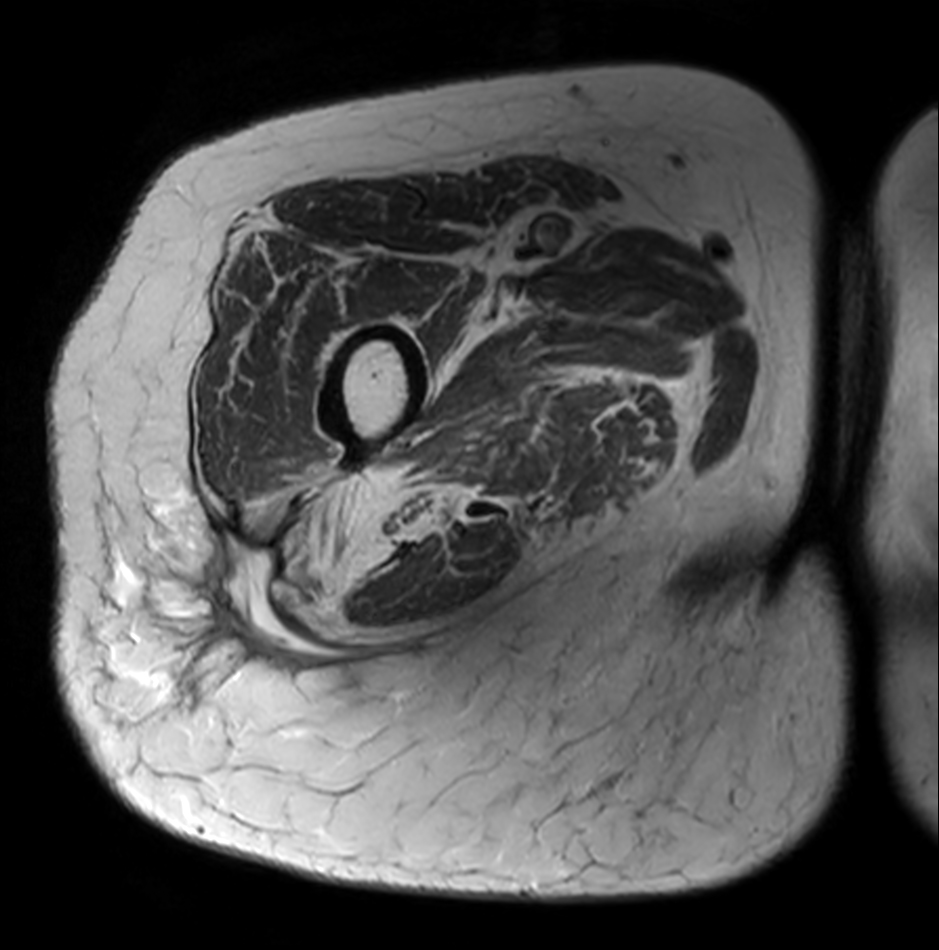

Axial T2w mDIXON XD TSE (In Phase)